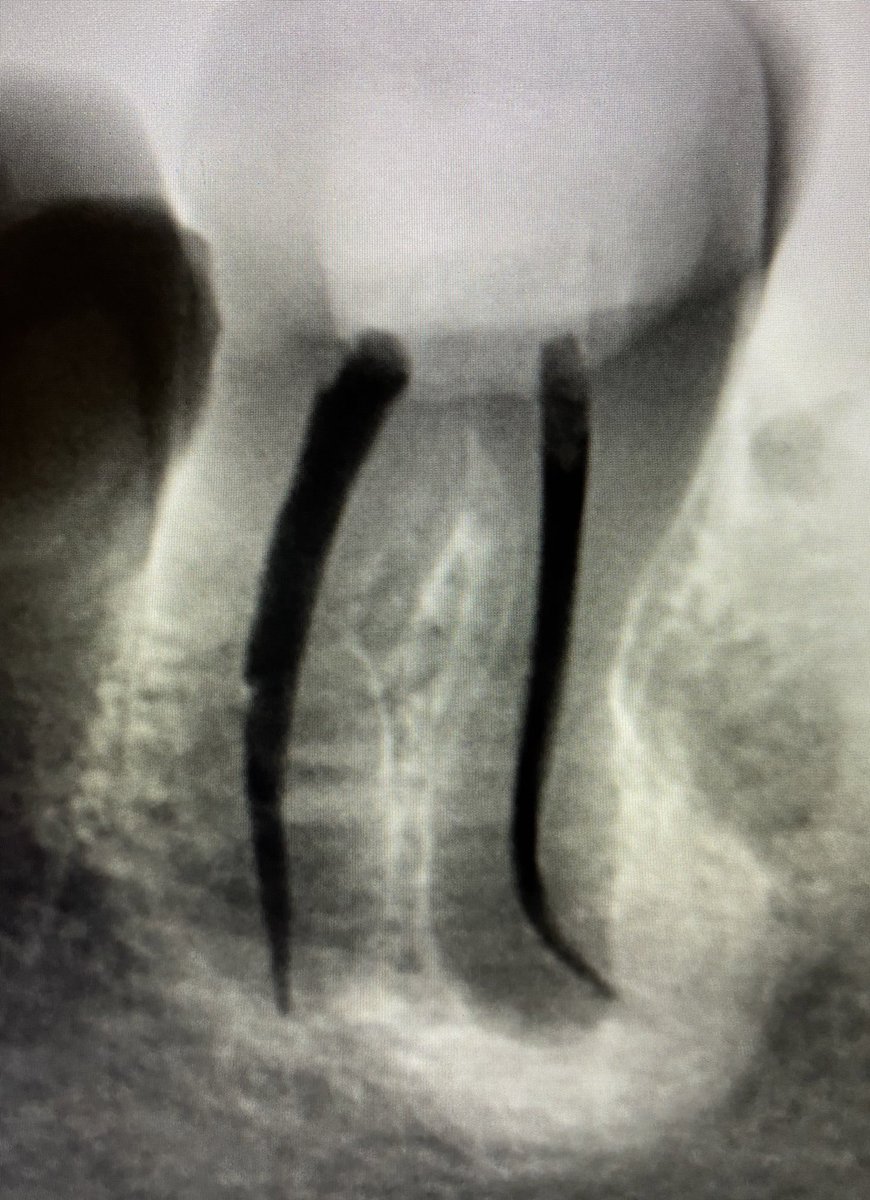

هنا يوجد. Large PA lesion

حضر المريض بضرسين مقرره للخلع من كذا عياده وابلغته انه طبعا بالامكان المحافظه عليه وتم ذلك في جلسه واحده